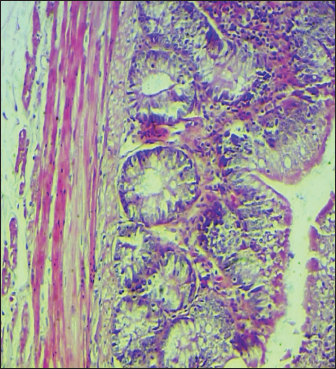

Histopathological study

The results noted in Figures 15 showed that chicks infected with S. enteritidis had edema among the muscular layer with atrophy of some intestinal villi. On the other hand, broilers infected with S. enteritidis and treated with C. myxa showed degeneration of intestinal glands with extensive inflammatory cell infiltration also mild sub-muscular edema, while with curcumin-treated group showed normal intestinal villi architectures, with hyperplasia of intestinal associated lymphoid tissue. The result noted a clear improvement in broilers that received C. myxa and curcumin showing normal intestinal villi with an increase in the number of goblet cells. The data of the present study confirmed the effectiveness of C. myxa and curcumin and especially the synergistic action between them in inhibiting the growth of S. enteritidis bacteria in poultry chickens, improving antioxidants and reducing free radicals, in addition to its action as a good anti-inflammatory at the blood level and suppressing the levels of cytokines that encourage inflammation and its role in improving intestinal tissues and making them close or similar to the health of broiler.

Fig. 1. Cross section of the intestine of poultry refers to normal histological architectures 100×. (H & E).

Fig. 4. Cross section of the intestine of poultry infected with S. enteritidis and treated with curcumin showing normal intestinal villi architectures, with hyperplasia of intestinal associated lymphoid tissue (200×, H & E).